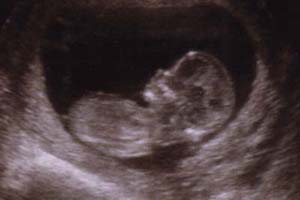

Au retour de notre voyage de noces, nous avons passé la 1ère échographie. Voici notre bébé en août 2002! ![]() Boubounou est sensé

naître le 21 février. Et oui, le jour où Bruno fêtera

ses 33 ans. Beau cadeau d'anniversaire!